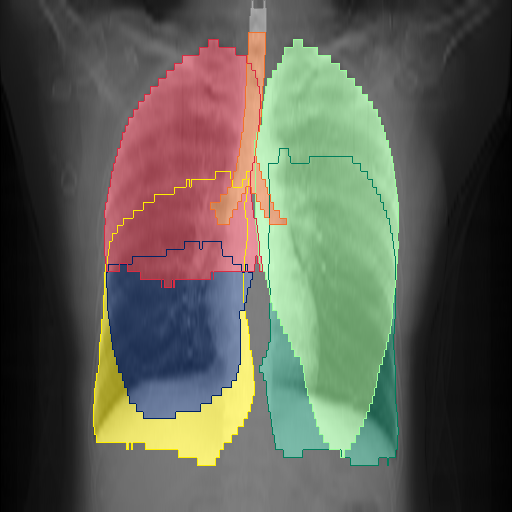

We show qualitative results for frontal projections in Fig. 2. We show a subset of classes belonging to the supercategories lungs, vascular systems, bones, and abdomen/digestive system. The predictions show minor deviations at the boundaries of the individual classes of the respiratory and vasculature system, while some inaccuracies become visible in the abdominal area. The qualitative results for the lateral projections are displayed in Fig. 2. Akin to the frontal view, the predictions show smoother borders but align with the ground truth. Apart from this, the segmentations provide matching insights on the thoracic anatomy with a slight deviation from the ground truth for both frontal and lateral views.

Fig. 2 shows quantitative segmentation results for frontal (top row) and lateral (bottom row) views. We display the class performances in the form of IoU (left), DICE (center), and Hausdorff distance (right) for each sample as a scatter plot with the mean performance for the classes shown by a line plot. Generally, we see performances for standard spinal classes, such as the thoracic vertebrae with average IoU-scores above 80%, while the average performance of rare vertebrae of the dataset belonging to the cervical and lumbar spine can drop down to 40%. In the frontal view, there exists more variance in thoracic vertebrae segmentation performance compared to the lateral view. Bone structures such as the sternum, clavicles, and scapula achieve IoUs in the mean from 85% to 95%. For ribs, we can see a noticeable performance drop for the anterior parts of the lower ribs independent of the side. The lower anterior ribs typically do not contain a large area, making them difficult to segment. This behavior is mirrored in the lateral view across the metrics. Abdominal classes can vary in segmentation quality as they occur in a nearly homogenous region. For example, while the liver or stomach are typically well-segmented, the duodenum and kidneys are more complex. Heart and Lung related classes show near-perfect segmentations with scores above 90% IoU. Breast tissue segmentation in comparison only achieves a mean of 70% mIoU. It can be noted that classes in the lateral view tend to have slightly better scores than their frontal counterparts.